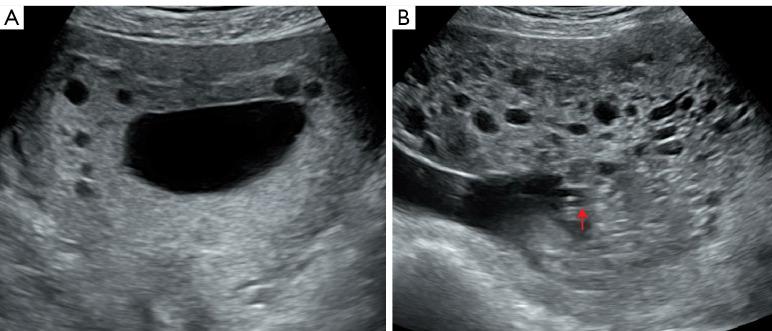

Of the 15 included patients, 4, 8, and 3 had PMD in early pregnancy (<13 W), mid-pregnancy (approximately 14-27 W), and late pregnancy (>28 W), respectively. Among the 15 patients, 5 successfully underwent delivery, thereby resulting in fetal survival; 3 experienced intrauterine death, 1 had a miscarriage, and 6 pregnancies were terminated. During early pregnancy, ultrasonographic manifestations of PMD included microscopic anechoic cystic areas in the placental parenchyma. In the second trimester, the placenta exhibited diffuse enlargement and thickening, with the placental parenchyma showing cellular anechoic cystic areas clearly separated from the surrounding normal placental tissue. As the pregnancy progressed, the cystic areas gradually reduced in the third trimester. Additionally, localized umbilical blood vessels showed tumorous lesions, sometimes accompanied by intravascular thrombosis. Some cases exhibited tortuosity and dilation in the umbilical vein.

https://cdn.ncbi.nlm.nih.gov/pmc/blobs/6751/11400704/6c95a1aec3ac/qims-14-09-6934-f1.jpg